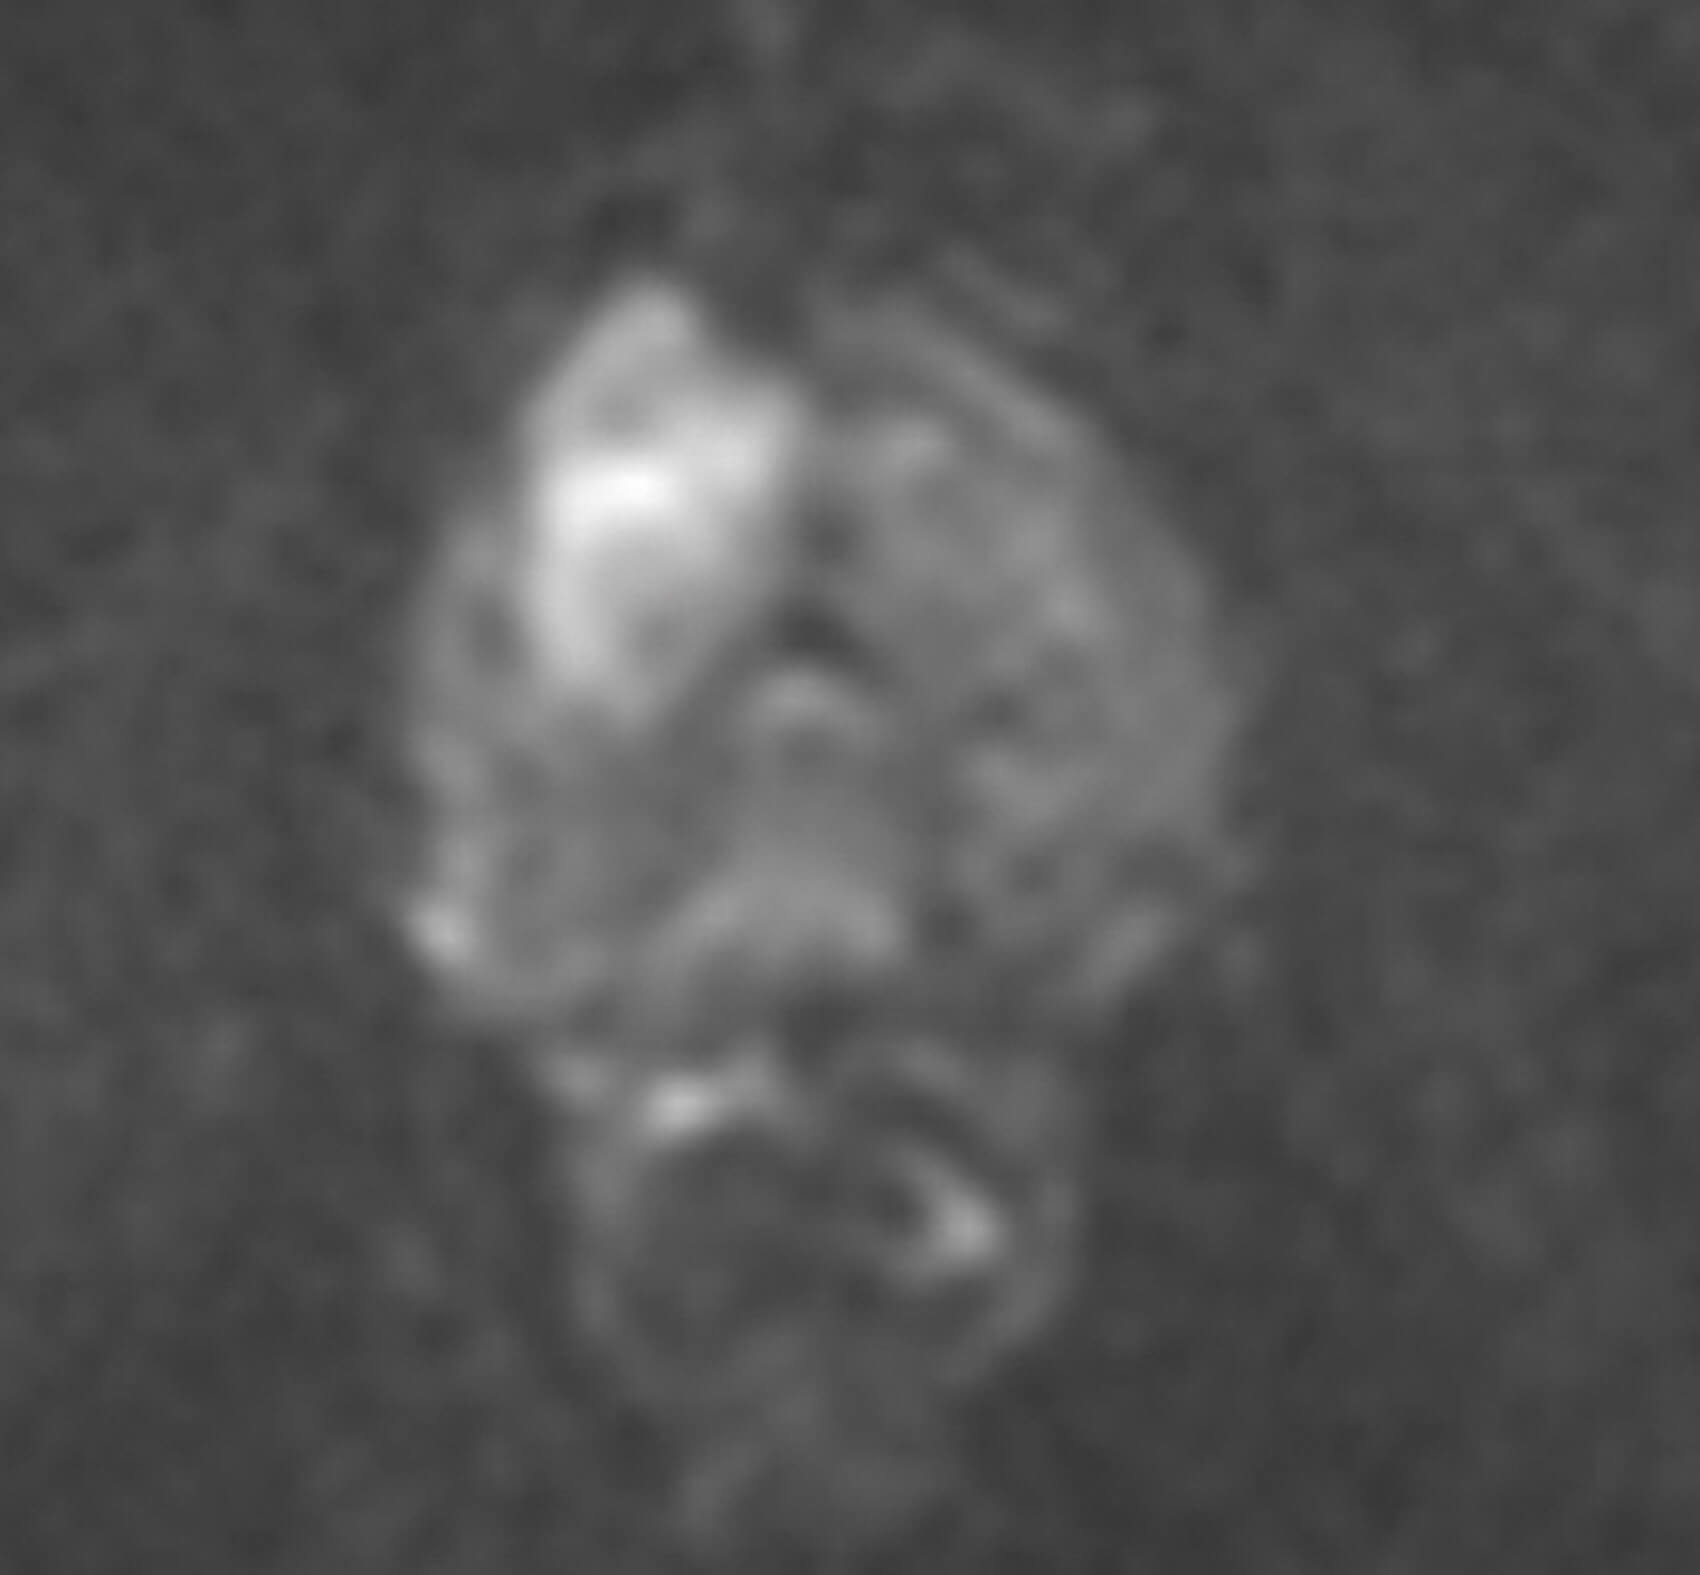

Figure 2.

Figure 3.

1 .Image 1 is the axial T2-weighted image of a PI-RADS 5 mid-gland lesion in the right transition zone. The lesion appears dark, measuring 19mm in diameter and would be T2bN0M0. Image 2 and image 3 is the same lesion demonstrated on the high b value (b1400) Diffusion weighted image (DWI) and the apparent diffusion coefficient (ADC) map respectively. Image 4 shows the same lesion with increased contrast uptake on the early dynamic contrast enhanced sequence (although contrast has limited role in the evaluation of the transition zone) [1].